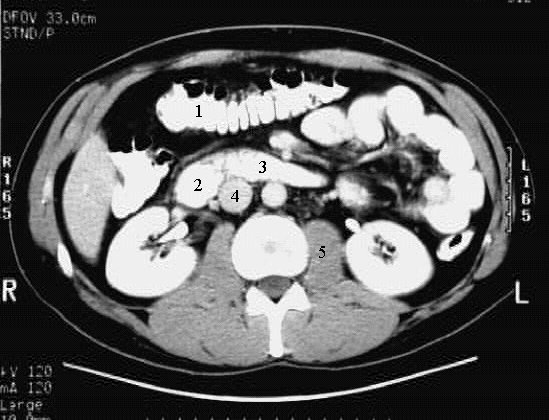

Abdomen- Abdomen Cross 6 :

1. Transverse Colon

2. Duodenum - junction of 2nd & 3rd parts

3. Duodenum - 3rd part

4. Inferior Vena Cava

5. Psoas Muscle